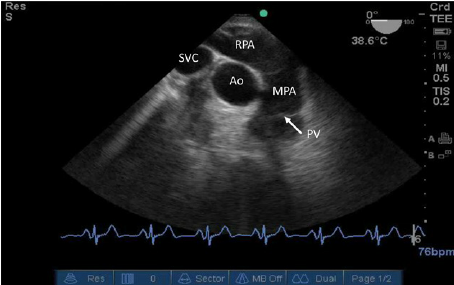

UE Aortic Arch short axis view

The round on top is the Aorti Arch

the curve in the botton is the Pulmonary Artery